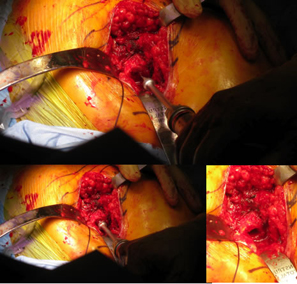

| Posterior approach. |

| Initial femoral neck resection high retained most of the neck. |

| Very tight on the reaming was going to push the limit on sizing for this patient. |

| Small Ben Hur was used to open for the ARC Awl. |

Rat tail rasp was then used as both a canal finder and to slightly enlarge the opening. This worked fairly well. |

| Small femoral canal and neck |

Awl goes in fairly easy |

| Starter rasp very tight fit. |

Size 1 rasp could not seat deep enough and would have to use 28 mm head decision made to switch to Apex Modular Stem |

| Only took about 8-10 minutes to prepare for Apex Modular |

Intra-operative x-ray helps check mechanical alignment and modular features allow for last minute fine tuning. Neck length adjusted. Stem fit like a custom implant. 2 prox x 10 mm. |